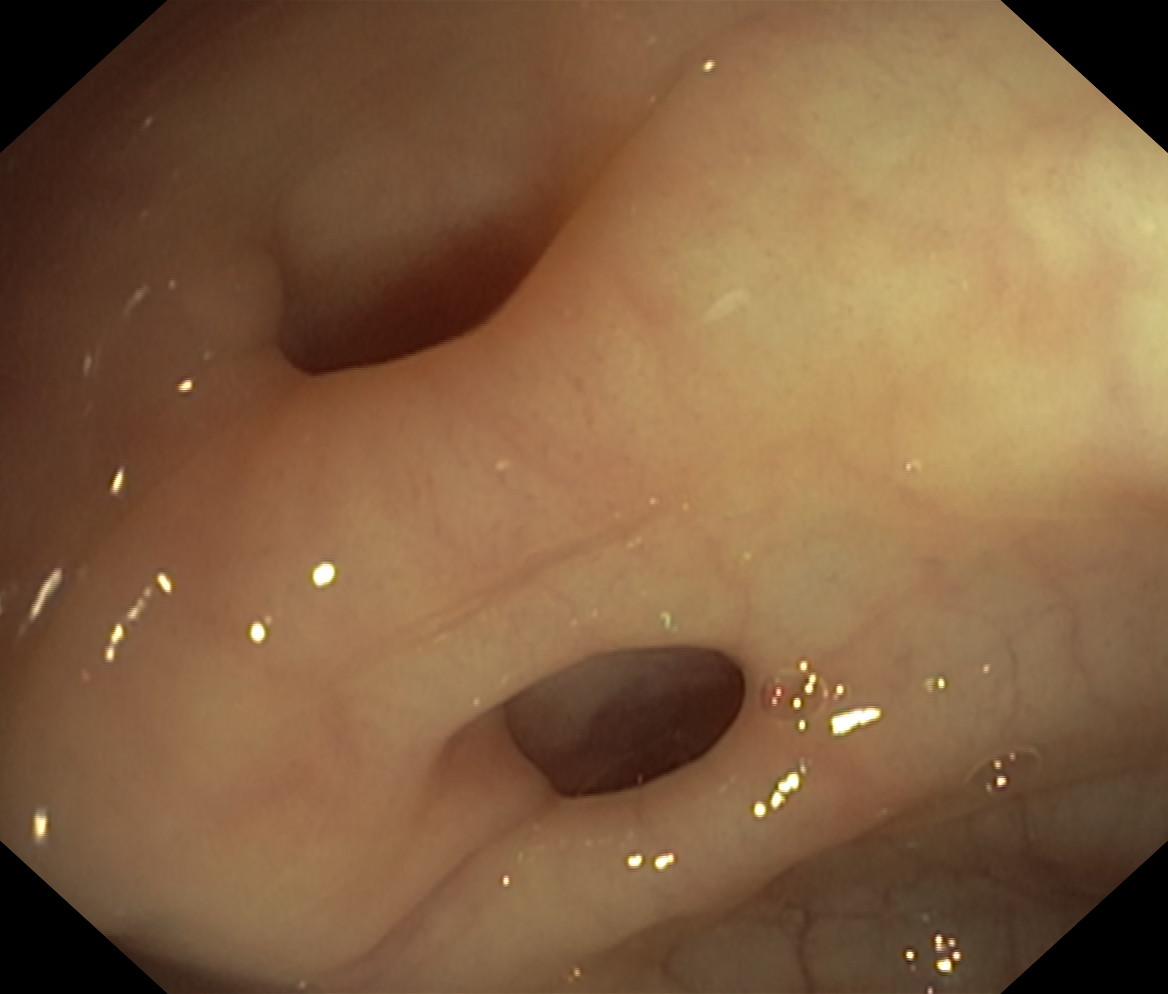

Uchyłki